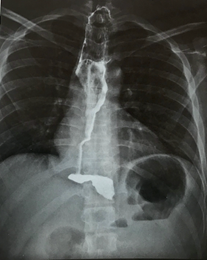

Figure 4:Radiological evidence of rectification of the esophagus.

The onset of the diet occurred on the first day of the postoperative in all cases. Hospital discharge on the second day (in 24 hours) in 100% of patients. Was considered as a successful treatment on three of the three patients. Applying the dysphagia score in the post-op, we find mean for dysphagia frequency 0.3 points, mean for dysphagia intensity 1 point and a global mean of 1.3 points. The global mean falls between the pre and postoperative dysphagia score, was 8.67 points, which represents a decline of 86.7%. The patient’s assessment of improvement in quality of life with their his own words revealed an average improvement of 93.33%, with 1 of the patients showed a 100% improvement in quality of life and the other two cases showed 90% improvements in quality of life. There was no clinically relevant gastroesophageal reflux. The mean follow-up time was 30.6 months (24-38 months). There was no long-term morbidity (Figure 4).